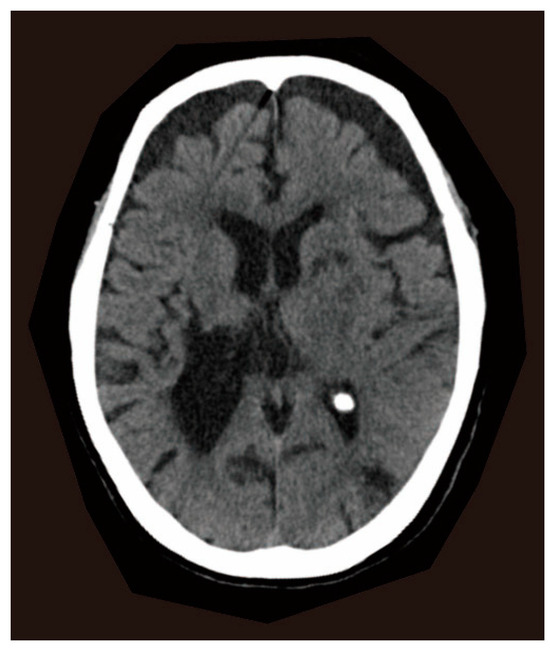

2. Case Report

2.1. Clinical Presentations